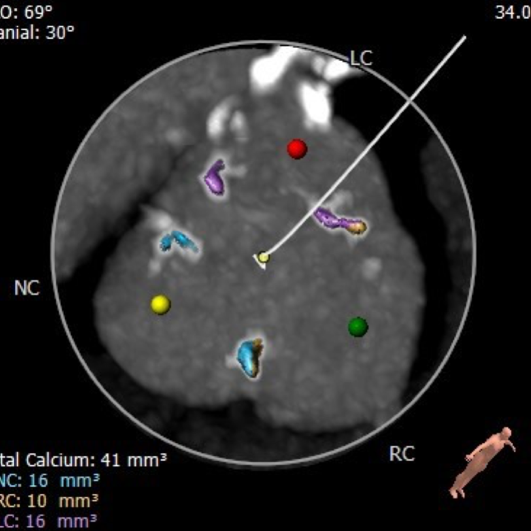

主动脉根部评估

CT 数据显示该患者为三叶式主动脉瓣